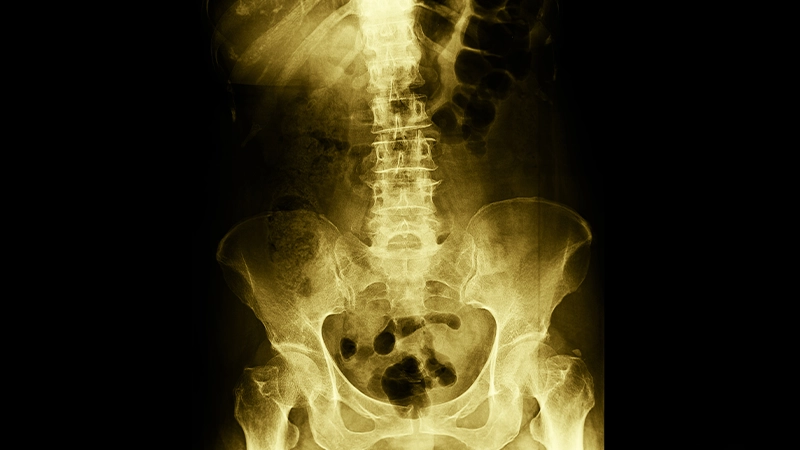

Diagnosis and Evaluation:

When assessing hip osteoarthritis, doctors take the patient’s history and perform a physical examination. They also examine the degree of pain and joint mobility. Imaging techniques such as X-rays, MRIs, or CT scans are often used to make a definitive diagnosis. These imaging techniques reveal the degree of arthritis, cartilage damage and osteophytes in the joint.